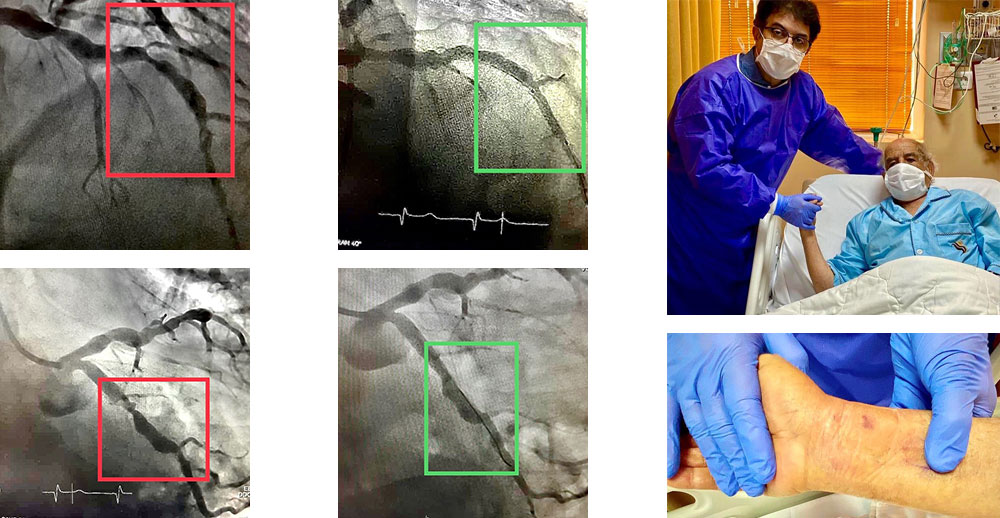

تنگی مدخل ورودی سیستم چپ عروق قلب

تا همین چند سال پیش راهی جز عمل جراحی اورژانس قلب باز نداشت. بیمار ما روز بعد از کارگذاری سه استنت در سیستم چپ به زندگی دوباره باز می گردد و قابل ترخیص است.

روش جدید درمان تنگی و گشادی متناوب شریان های قلب

با استنت هایی با قابلیت اتساع خود به خود، که منجر به شکل گرفتن و چسبیدن استنت در تمام طول به شدت نامنظم تنگی و گشادی رگ می شود. بیمار ۸۵ ساله ی ما، روز بعد از کارگذاری ۵ استنت در جریان آنژیوپلاستی از طریق شریان دست، قابل ترخیص است. بیمار فوق را به طور قطعی به جراحی قلب باز، ارجاع داده بودند.